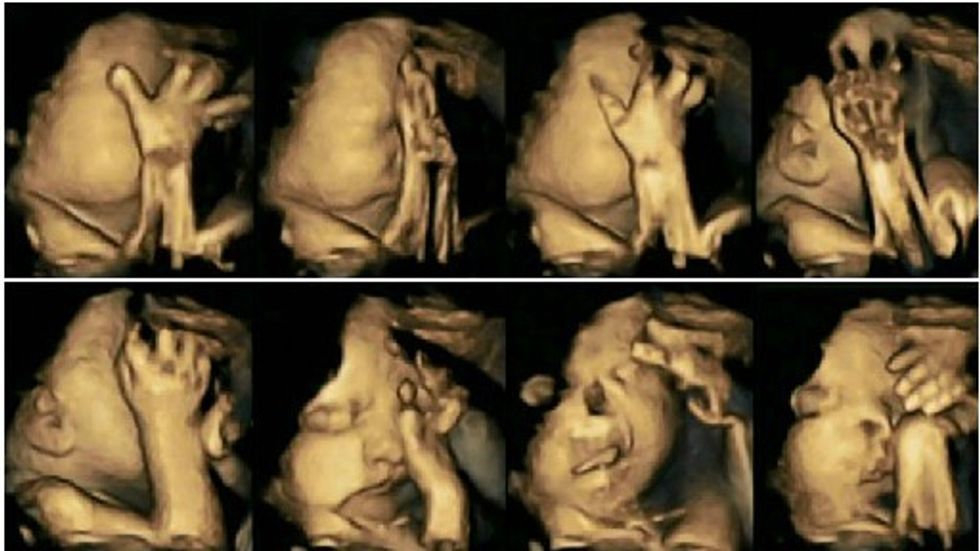

Dr Nadja Reissland ka studiuar lëvizjet me anë të një skaneri 4D ku ka regjistruar imazhet e mijëra lëvizjeve të foshnjave në barkun e nënës.

Studimi gjithashtu ka treguar se foshnjat e mbajtura nga duhanpirëset mund të kenë të vonuar zhvillimin e sistemit nervor qendror.

Bebet e nënave duhanpirëse